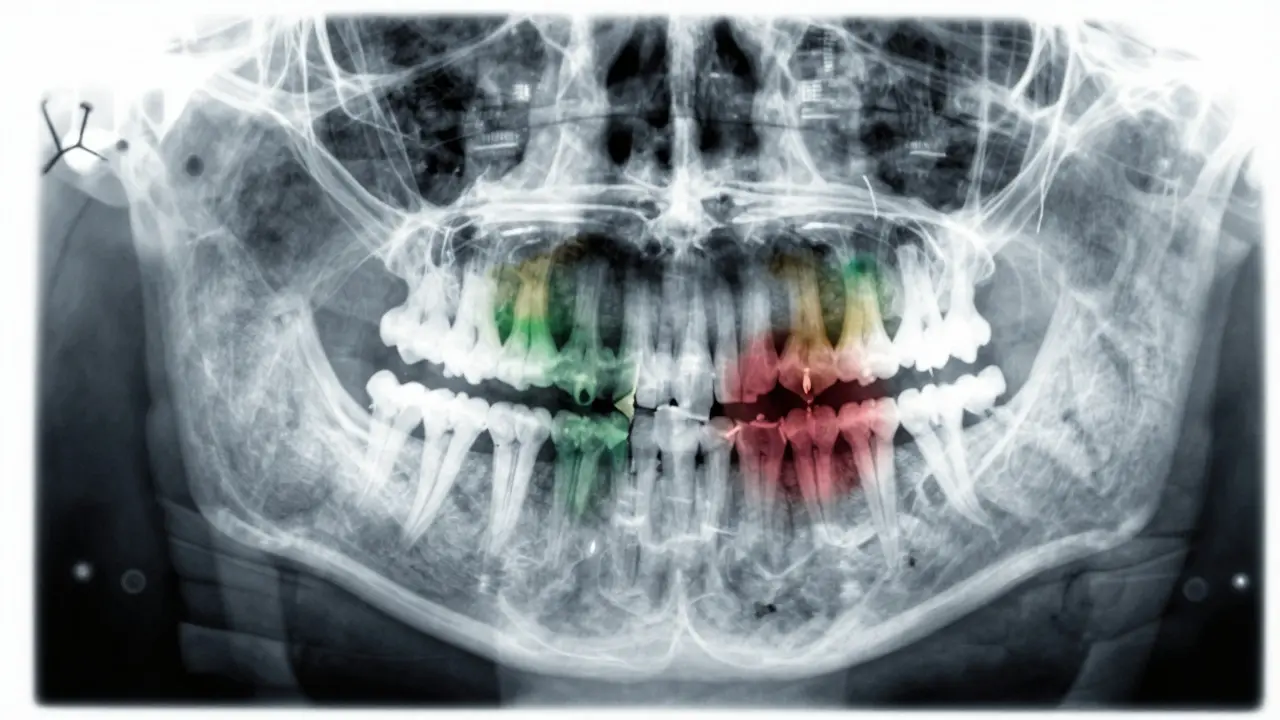

Když přijdete k zubaři, nebudete se divit, že vás nejprve očekává rentgen. Ten je klíčový. Ukáže, zda:

• Zůstal nějaký zubní kořen

• Je infekce ve čtvrti kolem kořene

• Je poškozeno i sousední zuby

• Je kost kolem zubu ještě zdravá

Rentgenový snímek zubu s viditelným poškozením kořene a infekcí.